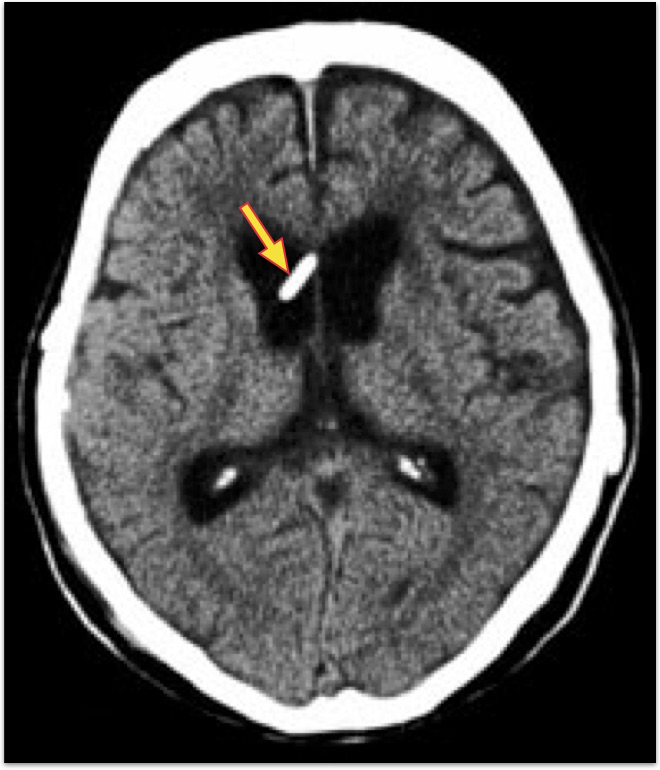

水頭症(二次生正常圧水頭症)

クモ膜下出血の慢性期に、交通性水頭症が発生することがある。これは、髄液の産生の亢進と吸収障害によると言われています。

<治療前:脳室拡大>

矢印は拡大した脳室

<VPシャント術後:脳室拡大消失>

矢印は挿入した脳室チューブ